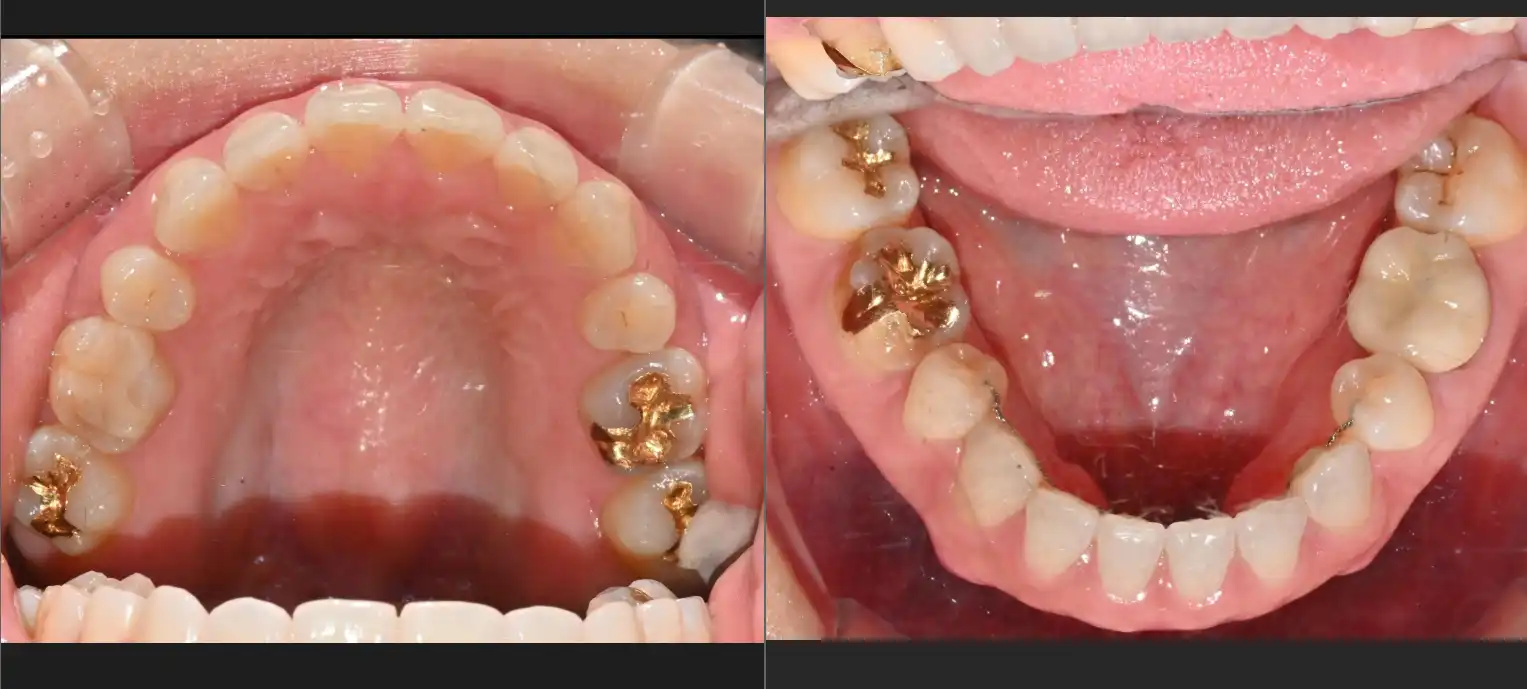

방문 인증 완료 #리엔장 당일식립 임플란트

전

후 임플란트 수술받았는데 안아프게 잘해주시고 원장님과 선생님들 모두 너무 친절하게 해주셔서 좋았습니다 수술비도 너무 가성비가 굿인거 갔습니다 매우 만족합니다

후 병원 위치가 역에서 내려 정말 1분이면 갈 수 있는 가까운 거리이고 시설 내부는 쾌적하고 깔끔하고 직원들까지 친절해서 좋았어요. 발치하고 당일식립은 못했지만 아프지 않게 잘 해주시네요.

방문 인증 완료 #리엔장 충치치료

후 마취도 안아프게 잘해주시고 충치도 깔끔하게 치료해주셨습니다. 시설도 좋고 다들 친절하셨어서 만족해요ㅎㅎ

전 깨진이와 충치치료로 방문하였는데 병원시설도 깨끗하고 좋고 친절한 응대도 좋았습니다. 고층이라 전용 엘리베이터도 있고 무료주차도되더라구요. 캐시닥에서 병원예약 처음이용했는데 만족합니다~~

후

후 우선 변원 워치가 너무 좋았고 간호사분들 원장님 친절하고 안아프게 해주셔서 치과 너무 무섭잖아요ㅎ 근데 편하게 치료 잘 받았습니다 시설도 깔끔하고 치료비도 비싸지 않고 대만족입니다